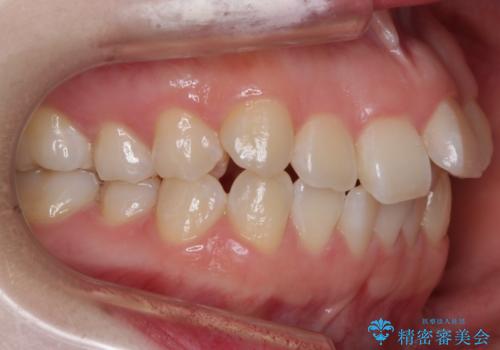

- 前歯のガタつきと口元の改善を主訴に来院されました。

なるべく目立たない装置が良いというご要望と、口元を引っ込めたいというご要望を両方達成するために今回はハーフリンガル装置を選択し治療計画の立案を行いました。

結果的に表の装置よりは期間が掛かりましたが、口元もしっかり下がり韓国美人な横顔になったと患者様にも喜んでいただけました。